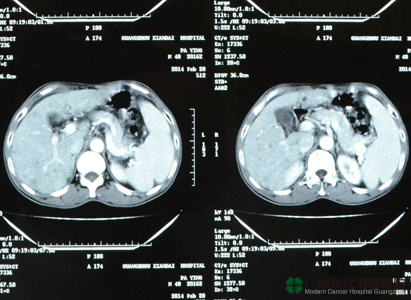

ครอบครัวคุณอินและเพื่อนๆ ให้กำลังอยู่ข้างๆ เขาตลอด พวกเขาวิ่งวุ่นไปทุกๆ ที่ เพื่อค้นหาการรักษาที่ดียิ่งกว่าให้แก่คุณอิน ต่อมามีเพื่อนคนหนึ่งแนะนำให้เขาไปรักษาที่ประเทศจีน เนื่องจากประเทศจีนมีโรงพยาบาลที่รักษามะเร็งโดยเฉพาะ---โรงพยาบาลมะเร็งสมัยใหม่กว่างโจว และมีสำนักงานอยู่ที่กรุงเทพประจำประเทศไทย คุณอินจึงโทรศัพท์ไปสอบถามที่สำนักงานเพื่อทำความเข้าใจ ซึ่งพอดีกับที่มีเจ้าหน้าที่ของเราไปปฏิบัติงานที่เชียงใหม่ จึงสามารถพูดคุยกับเขาโดยตรง หลังจากที่ฟังเจ้าหน้าที่อธิบายอย่างละเอียด เขาได้ทราบเทคโนโลยีการรักษาที่ทันสมัยผลข้างเคียงน้อย เห็นผลเร็ว ครั้นแล้วเขาจึงมีความหวัง คุณอินจึงได้มาที่โรงพยาบาลมะเร็งสมัยใหม่กว่างโจว แพทย์ได้ทำการตรวจทุกด้าน และประชุมร่วมกับทีมผู้เชี่ยวชาญ จึงได้กำหนดวิธีการรักษาตามสภาพความเป็นจริง และตัดสินใจทำการักษาแบบบูรณาการ โดยใช้วิธีหลักๆ คือการรักษาแบบเฉพาะจุดผ่านหลอดเลือด นั้นเป็นวิธีการรักษาที่ไม่เคยไม่ยินในประเทศไทย บาดแผลเล็ก ผลข้างเคียงน้อย หลังจากทำการรักษาแบบเฉพาะจุดผ่านหลอดเลือดสองครั้ง ผลซีทีสแกนปรากฏว่าเนื้อร้ายมีขนาดเล็กลง อาการที่รู้สึกไม่สบายก็หายไป น้ำหนักก็เพิ่มขึ้นเป็น 52กิโลกรัม เขารู้สึกว่าตนเองกลับมาเป็นเหมือนคนปกติอีกครั้ง คุณอินบอกเราอย่างดีใจ

ผลซีทีสแกนหลังการรักษา